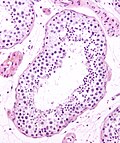

Microscopic:

- Delicate anastomosing channels lined by cuboid epithelium.

Rete testis

- Receives stuff from the tubules.

- Occasionally afflicted by adenomatous hyperplasia of the rete testis.

- Very rarely give rise to an adenocarcinoma of the rete testis.

- May be involved by seminoma.